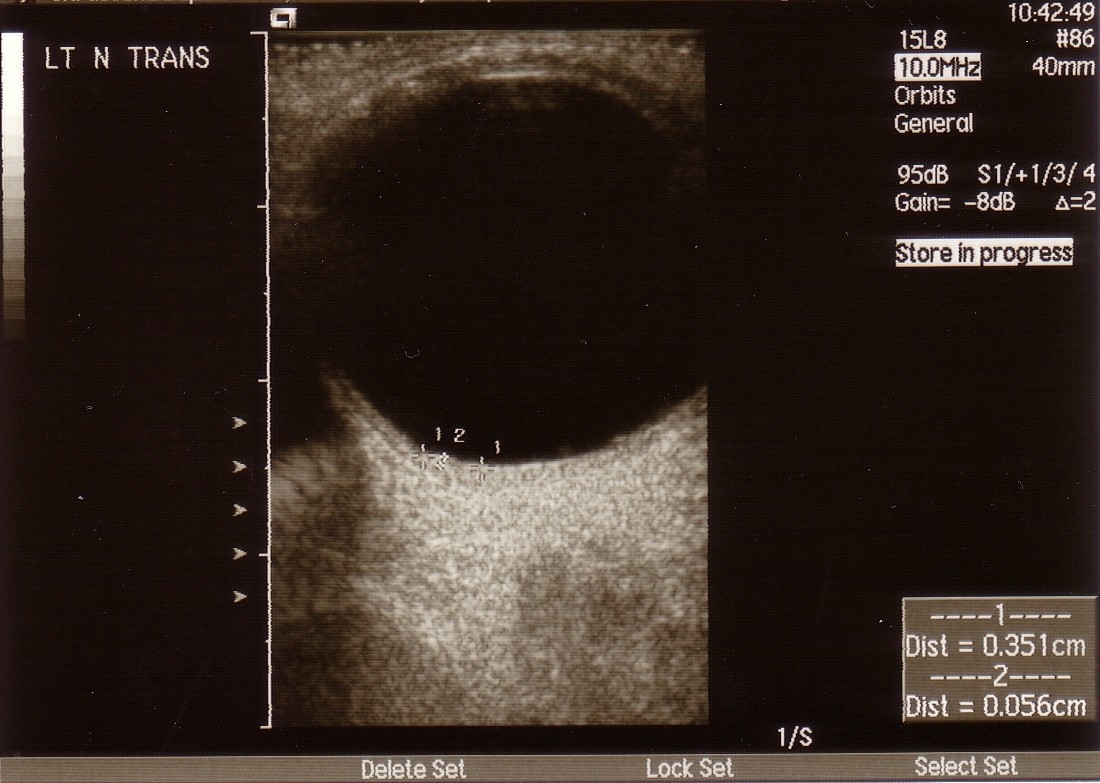

Figure 3From: Ocular metastases from HER2 positive breast carcinoma and the response to combination therapy with Paclitaxel and Trastuzumab: a case reportB-scan 8 months post-treatment showing the reduced dimensions of the inferonasal lesion (3.5 mm transverse, 2.3 mm longitudinal base and 0.6 mm elevation).Back to article page